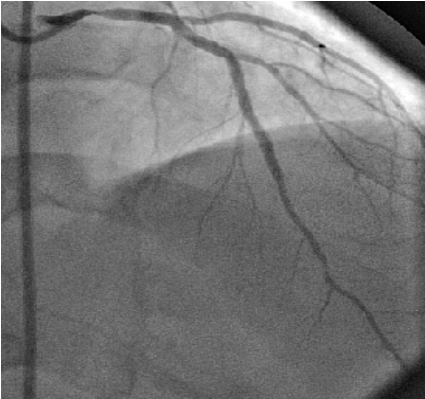

Case 1: A 55-year-old diabetic and hypertensive male presented with angina, with a Canadian Cardiovascular Society (CCS) score of three. His diagnostic coronary angiogram showed 30–40% lesion in proximal left main stem, critical disease in mid-LAD and diagonal branch (bifurcation lesion), moderate disease in mid-right coronary artery (RCA) and normal left ventricular systolic function (Figure 1). He underwent PCI to LAD and diagonal. A 7 French EBU (Medtronic, Inc. Minneapolis, USA) guide catheter was selected. Both LAD and diagonal branch were wired and predilated with a 2x15 mm Sequent balloon (B Braun, Melsungen, Germany) and a 2.5x33 Cypher Select plus stent (Cordis, Johnson and Johnson, USA) was deployed in proximal to mid-LAD at 16 ATM. A bare metal stent 2.5x9 mm Clear flex (Clear Stream Technologies Ltd. Wexford, Ireland) was deployed distal to the first stent to cover the remaining stenosis. Finally, diagonal branch was dilated across the stent struts. During the procedure guide position was carefully watched.

Figure 1: Diagnostic angiogram LAO caudal view showing plaquing in left main coronary artery with significant disease in mid-left anterior descending coronary artery (Case 1).